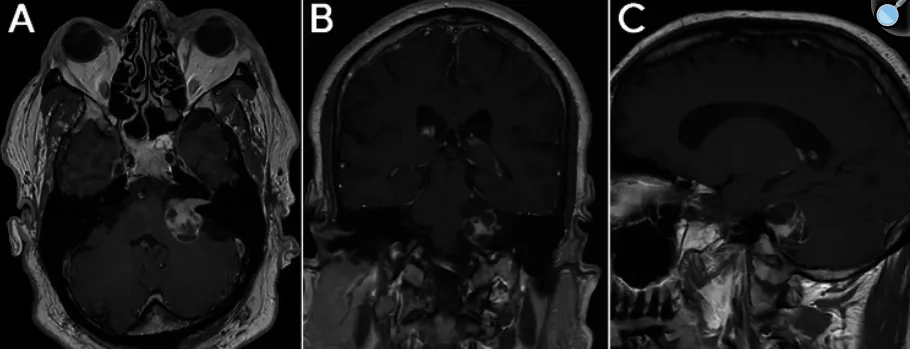

患者为一名59岁男性,主要临床表现为进行性加重的左侧听力严重下降。头颅磁共振成像(MRI)检查显示,其左侧内听道及桥小脑角区存在一个大小约2.9厘米的占位性病变,该病变呈部分囊性,并伴有轻度脑干受压征象,符合囊性听神经瘤的影像学诊断。

图1. 术前轴位、冠状位及矢状位MRI图像,显示一个大小约3厘米、部分囊性、注射对比剂后明显强化的病变,病变扩大并充满了内听道及桥小脑角区,符合Koos 4级听神经瘤。